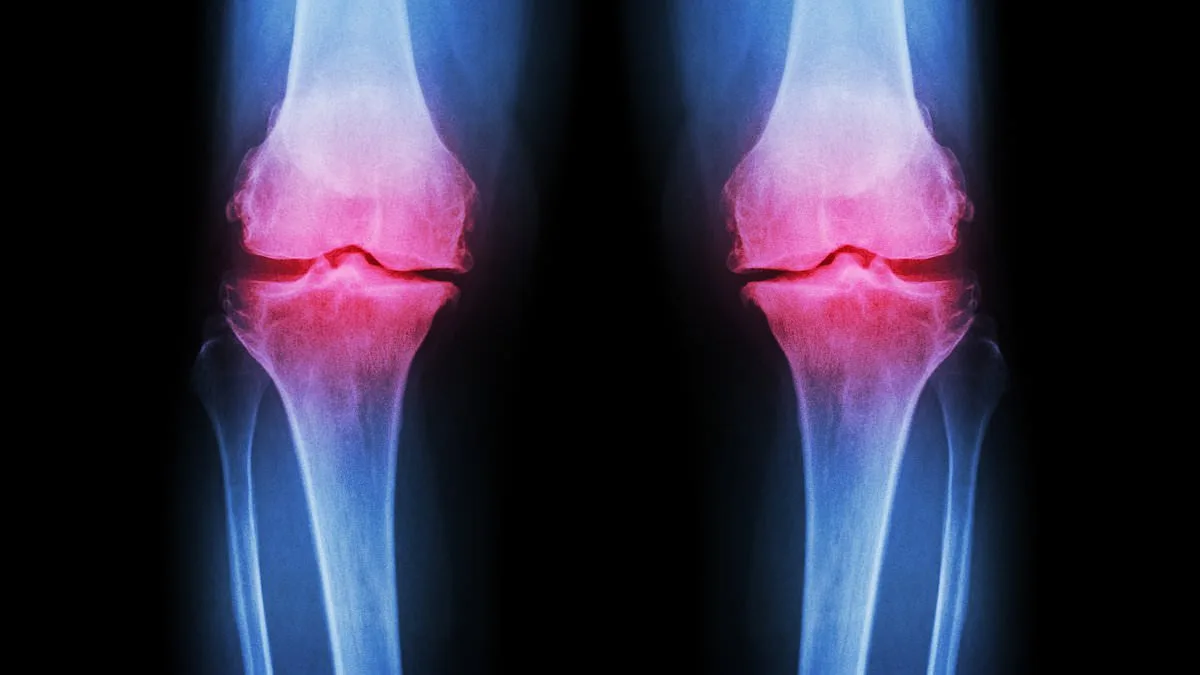

Osteoarthritis, which affects approximately 10 million people in the UK, is typically associated with aging. However, cases in patients under 45 are rising sharply, with some estimates suggesting a 25% increase since 2015. This trend is partly attributed to post-traumatic osteoarthritis, a condition caused by fractures that disrupt joint mechanics. For example, ankle or knee injuries from repetitive high-impact exercises can lead to uneven weight distribution, causing cartilage to wear down prematurely. 'It's a ticking time bomb,' said Dr. Atiqah Aziz, a senior researcher at the National Orthopaedic Centre. 'Young people are developing symptoms that would normally take decades to manifest in older adults, and the damage is often irreversible by the time they seek help.'